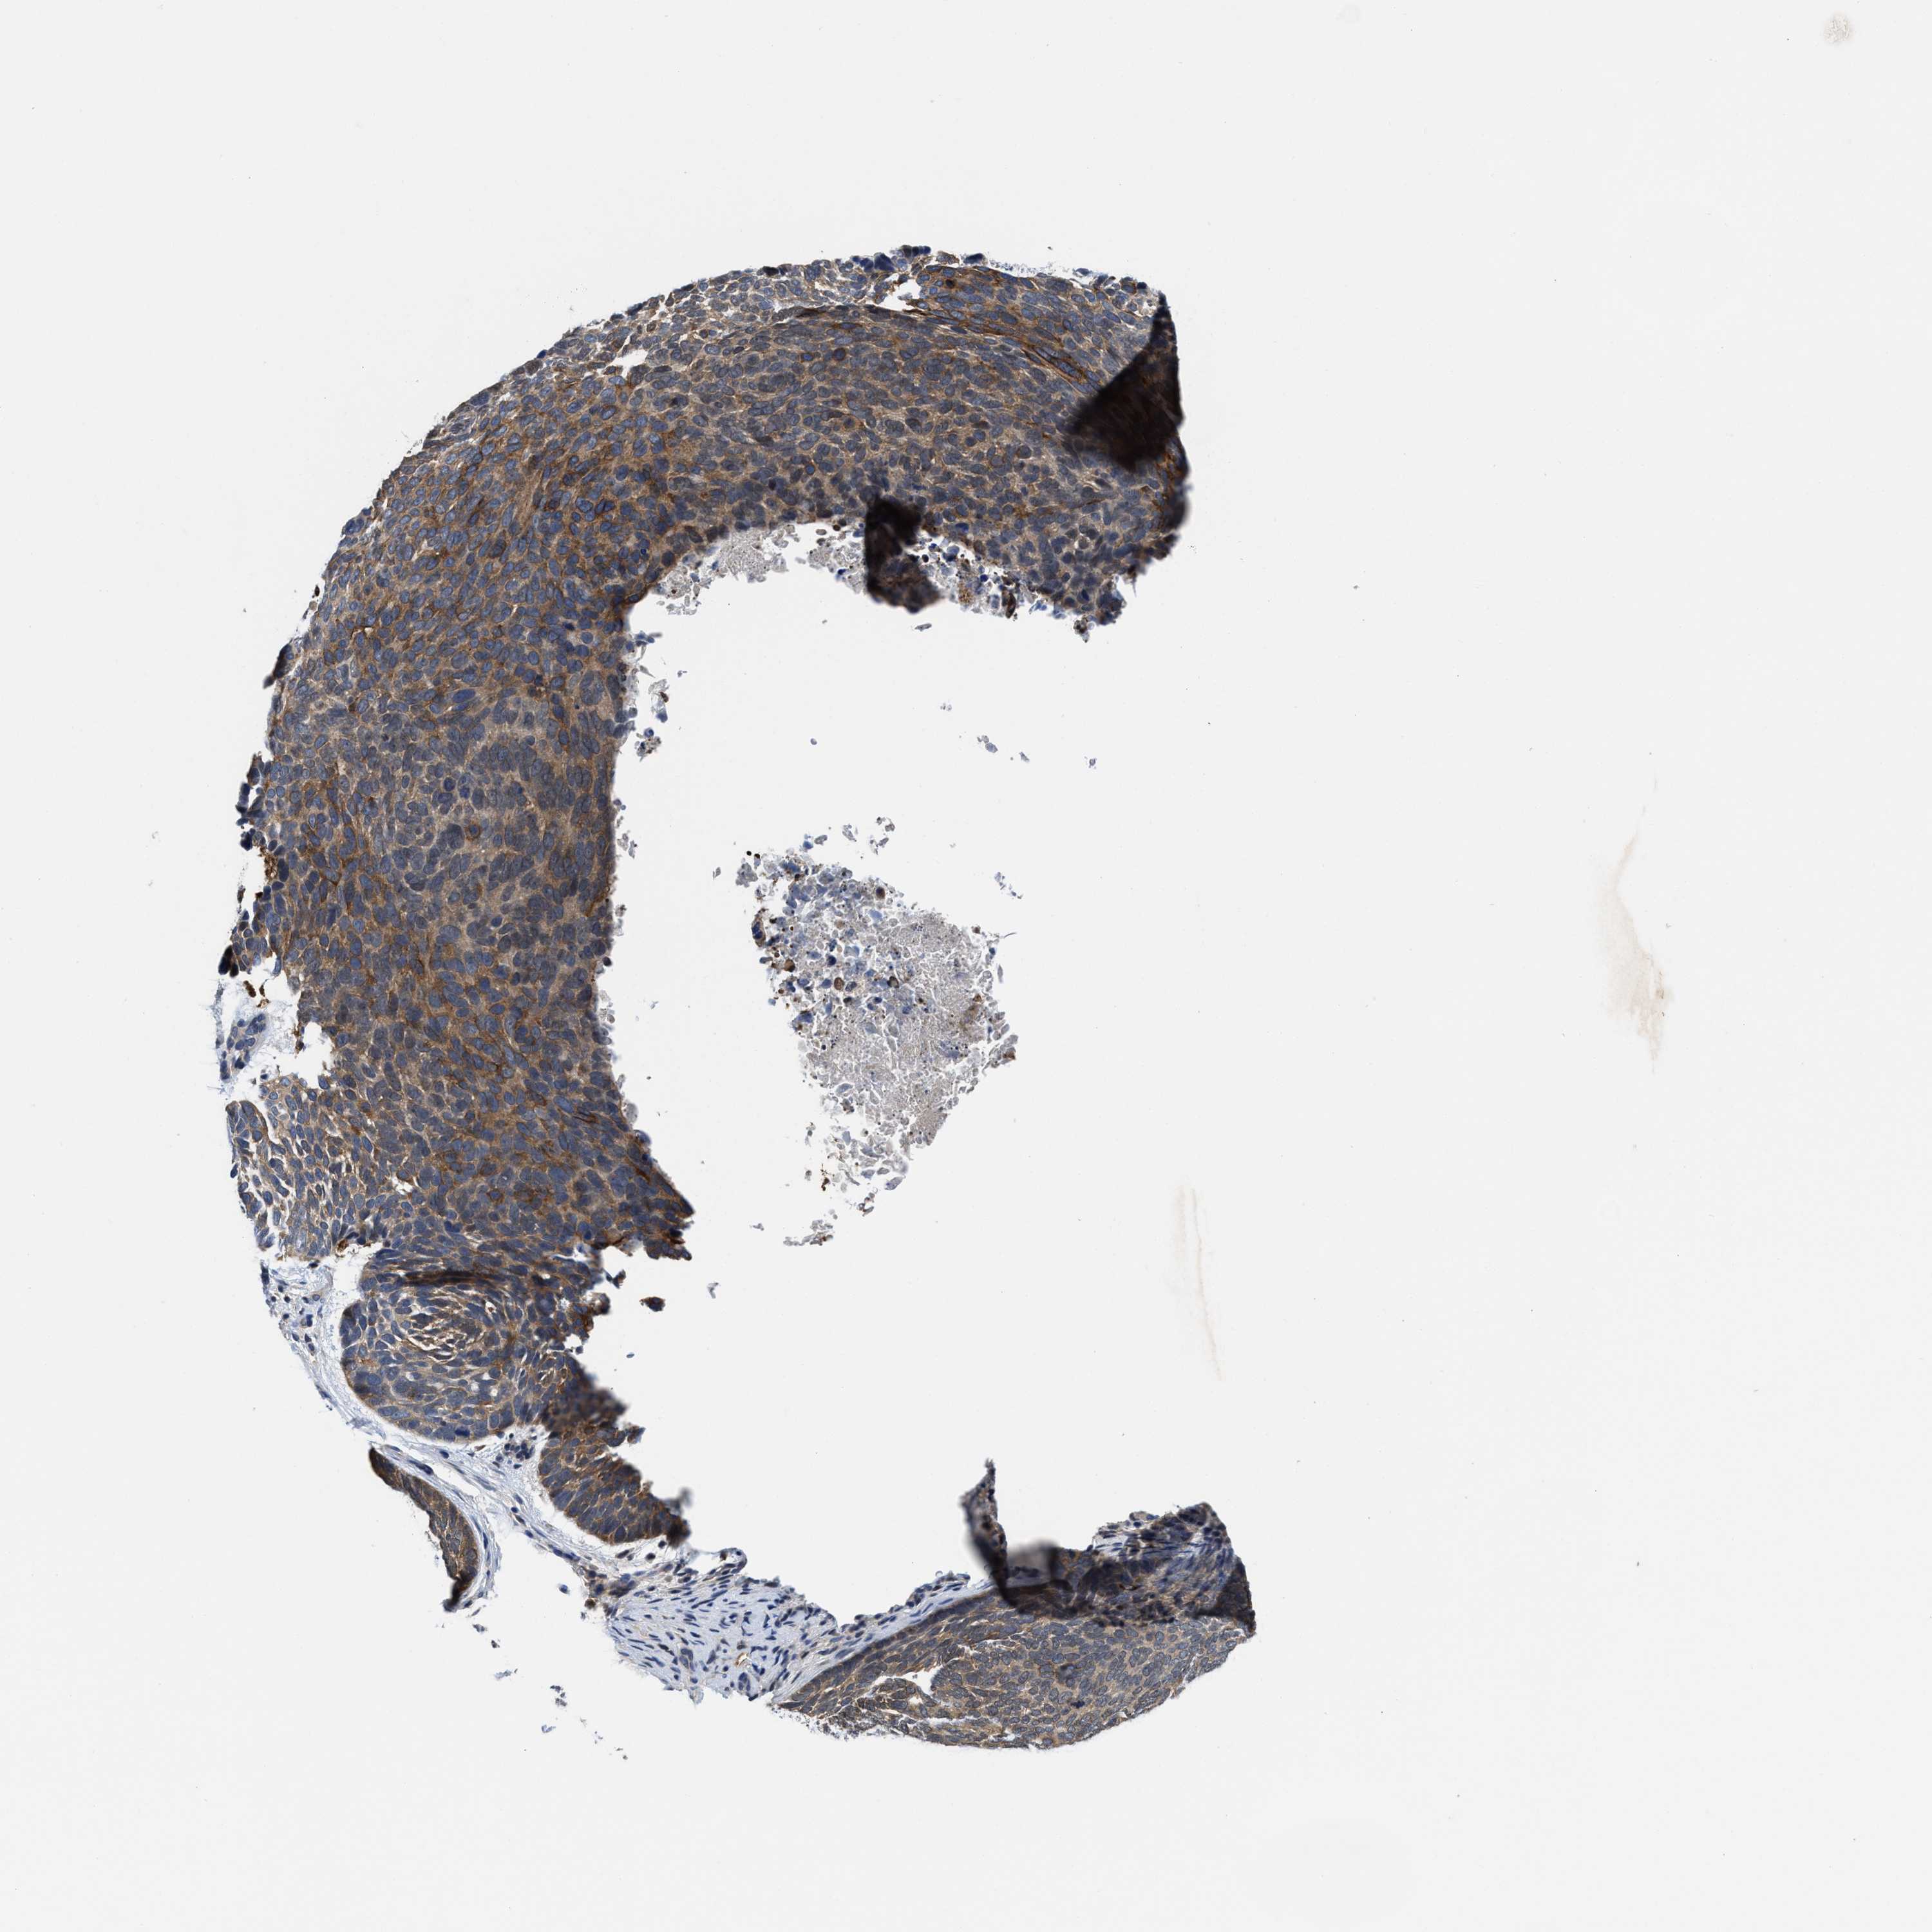

SKIN CANCER - Protein expressioni

A mouse-over function shows sample information and annotation data. Click on an image to view it in a full screen mode. Samples can be filtered based on level of antibody staining by selecting one or several of the following categories: high, medium, low and not detected. The assay and annotation is described here.

Antibody staining in the annotated cell types in the current human tissue is reported as not detected, low, medium, or high, based on conventional immunohistochemistry profiling in selected tissues. This score is based on the combination of the staining intensity and fraction of stained cells.

Each image is clickable and will lead to virtual microscopy that enables deeper exploration of all samples and also displays staining intensity scores, fraction scores and subcellular localization as well as patient and tissue information for each sample.

Antibody HPA020192

Basal cell carcinoma